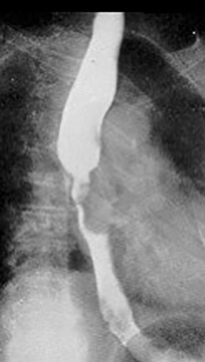

What are the classic barium swallow signs of achalasia?

Bird’s beak sign, string sign, corkscrew esophagus.

What are the two growth patterns of esophageal carcinoma?

Infiltrating and proliferating.

What is the radiographic appearance of the infiltrating type of esophageal carcinoma?

Irregular narrowing, mucosal destruction, esophageal dilation above lesion.

What is the radiographic appearance of the proliferating type of esophageal carcinoma?

Plaque-like lesions causing filling defects.

What is 'shelving' in esophageal carcinoma?

Sharp, shelf-like demarcation between normal and diseased esophagus (classic infiltrative sign).

What are the best imaging studies for esophageal carcinoma?

Barium swallow (if patient can swallow); CT for staging and treatment planning.